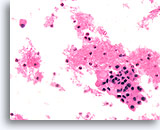

Afbeelding 14

Benigne, hyperplastisch/adenomatoïde nodule, schildklier FNA, celblok.

Let op het afgeplatte cytoplasma in e microfollikels vergeleken met het kubusvormige tot cilindrische cytoplasma van het macrofolliculaire epitheel linksboven. Let ook op het waterige colloïde in één follikel (pijl) vergeleken met het dicht opeengepakte colloïde in de microfollikels.

40X

Afbeelding 14

Benigne, hyperplastisch/adenomatoïde nodule, schildklier FNA, celblok.

Let op het afgeplatte cytoplasma in e microfollikels vergeleken met het kubusvormige tot cilindrische cytoplasma van het macrofolliculaire epitheel linksboven. Let ook op het waterige colloïde in één follikel (pijl) vergeleken met het dicht opeengepakte colloïde in de microfollikels.

40X